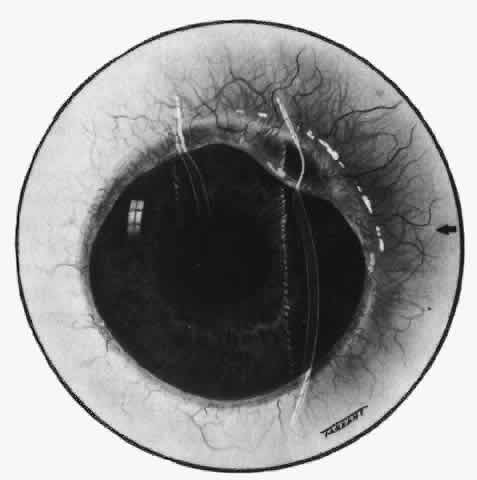

Simple and nodular episcleritis differ in their clinical courses, but in both the edema and infiltration are entirely within the episcleral tissues. The sclera is not involved. The maximum congestion is in the superficial episcleral network, with some slight congestion of the conjunctival vessels and deep episcleral vessels (Fig. 10). The intraocular structures are not involved in either variety, nor is the visual acuity affected. Anterior segment fluorescein angiography reveals a normal vascular pattern but a very rapid flow rate, with the whole transit of the dye being completed within 2 or 3 seconds (Figs. 11 and 12).

Fig. 10. Maximum congestion in the superficial vascular plexus in episcleritis. The conjunctival and deep episcleral networks are separated from the deep plexus by edema and infiltration in the episcleral tissue. (Watson PG, Hayreh S, Awdry P: Episcleritis and scleritis. Br J Ophthalmol 52(3):278–279, 1968)

Fig. 11. Anterior segment fluorescein angiogram of a 45-year-old woman with simple episcleritis. At first transit of dye, all the vessels are dilated and filling simultaneously. However, the vascular pattern is not disturbed.

Fig. 12. Angiogram of the same 45-year-old woman in Figure 11 one second later. Within 1 second, all the vessels are filled and there is even, venular filling except in the deep episcleral plexus. This is the rapid filling pattern seen in all forms of episcleritis and in diffuse anterior scleritis.

The redness of simple episcleritis may be intense, varying from a fiery-red or a brick-red discoloration to a mild red flush, but it does not have the bluish tinge that is seen in scleritis. The distribution is usually sectorial but can involve the whole anterior segment of the globe. The episcleral vessels are engorged but retain their normal radial position and architecture (Figs. 13 and 14; Color Plate 1A). In simple episcleritis, there is a diffuse edema of the episcleral tissues. These tissues are sometimes infiltrated with gray deposits that appear yellow in red-free light. Surprisingly, the eye is rarely tender to the touch.

Fig. 13. Infiltration of the episclera in which the superficial episcleral vessels show maximal congestion. Conjunctival vessels are slightly congested, as is the deep episcleral plexus, whose irregular criss-cross pattern can be seen deep to the radially arranged superficial episcleral plexus.

Fig. 14. Diffuse inflammation. Superficial vessels are maximally engorged and retain their radial pattern and architecture. (See Figures 27 and 34.) (Watson PG: Connective tissue disorders and the eye. In: Recent Advances in Ophthalmology, Vol 5, pp 214–277. London, Churchill-Livingstone, 1975)